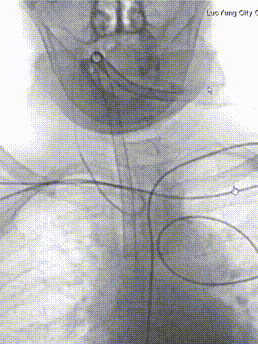

经桡动脉送入260cm泥鳅导丝,125cm西蒙动脉导管同轴输送7F EasyRadial™输送导管至右侧颈内动脉C1段远端。

200cm微导丝导引1.0*15mm 输送型球囊扩张导管送至右侧颈内动脉末端狭窄处。

200cm微导丝引导预塑形45°微导管超选至动脉瘤内。

沿微导管填入第一枚可解脱弹簧圈 6mm*15cm。

瘤体远端填塞良好,瘤体近端仍有造影剂充盈。

依次填入10枚弹簧圈(5mm*10cm两枚、3mm*6cm三枚、4mm*4cm一枚、3mm*4cm一枚、2.5mm*8cm一枚、1.5mm*1cm两枚)。

将球囊扩张导管置于狭窄处,由远端向近端给予球囊扩张成型处理。

扩张满意后,造影显示狭窄明显改善。

填入最后一枚弹簧圈 1.5mm*1cm。

造影显示动脉瘤致密栓塞,未向动脉内凸出,载瘤动脉通畅,无需释放支架。